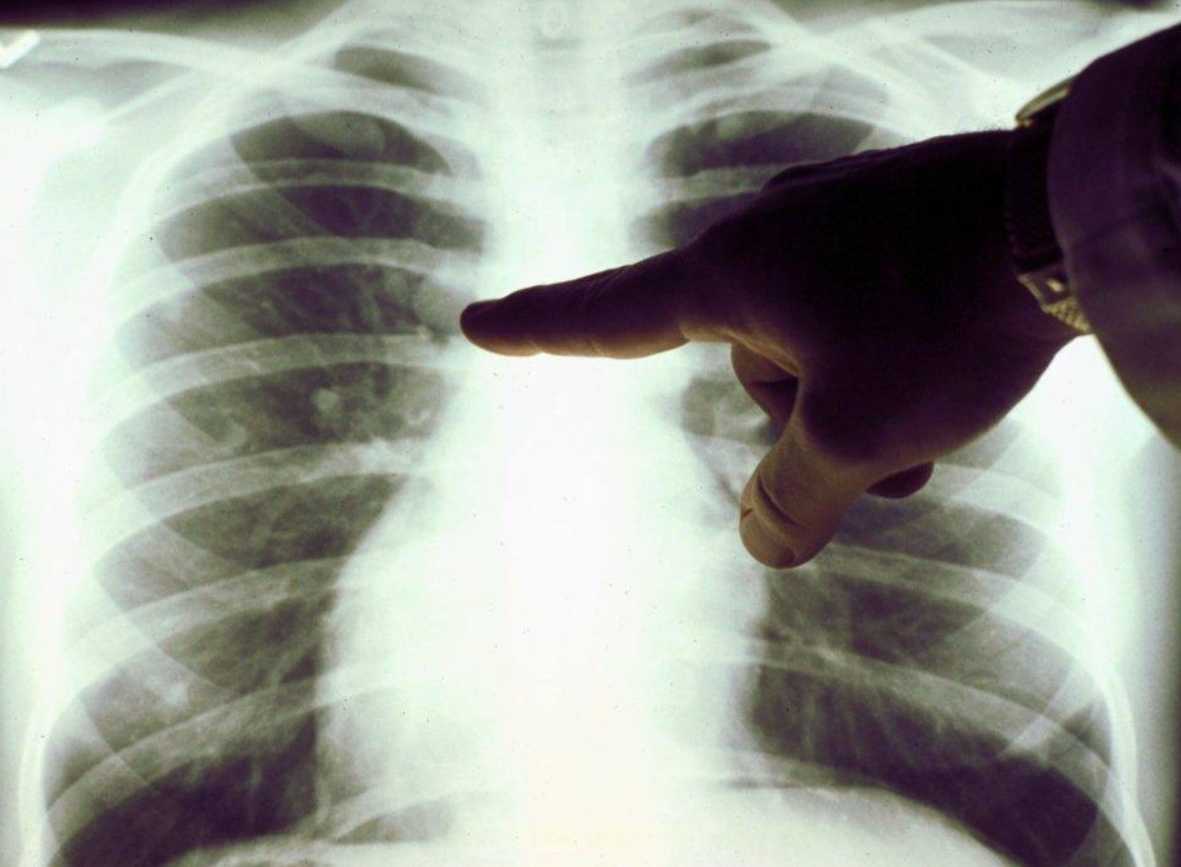

Диагностика

К диагностическим мероприятиям при бронхите относятся:

Также для определения наличия хрипов и свистов проводится аускультация (прослушивание) легких.